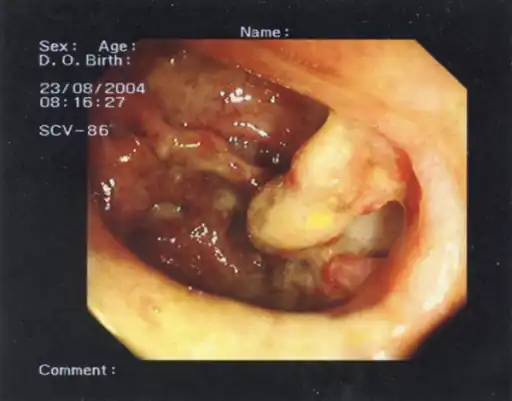

Colonoscopy is contraindicated, as it may rupture the dilated colon resulting in peritonitis and septic shock.